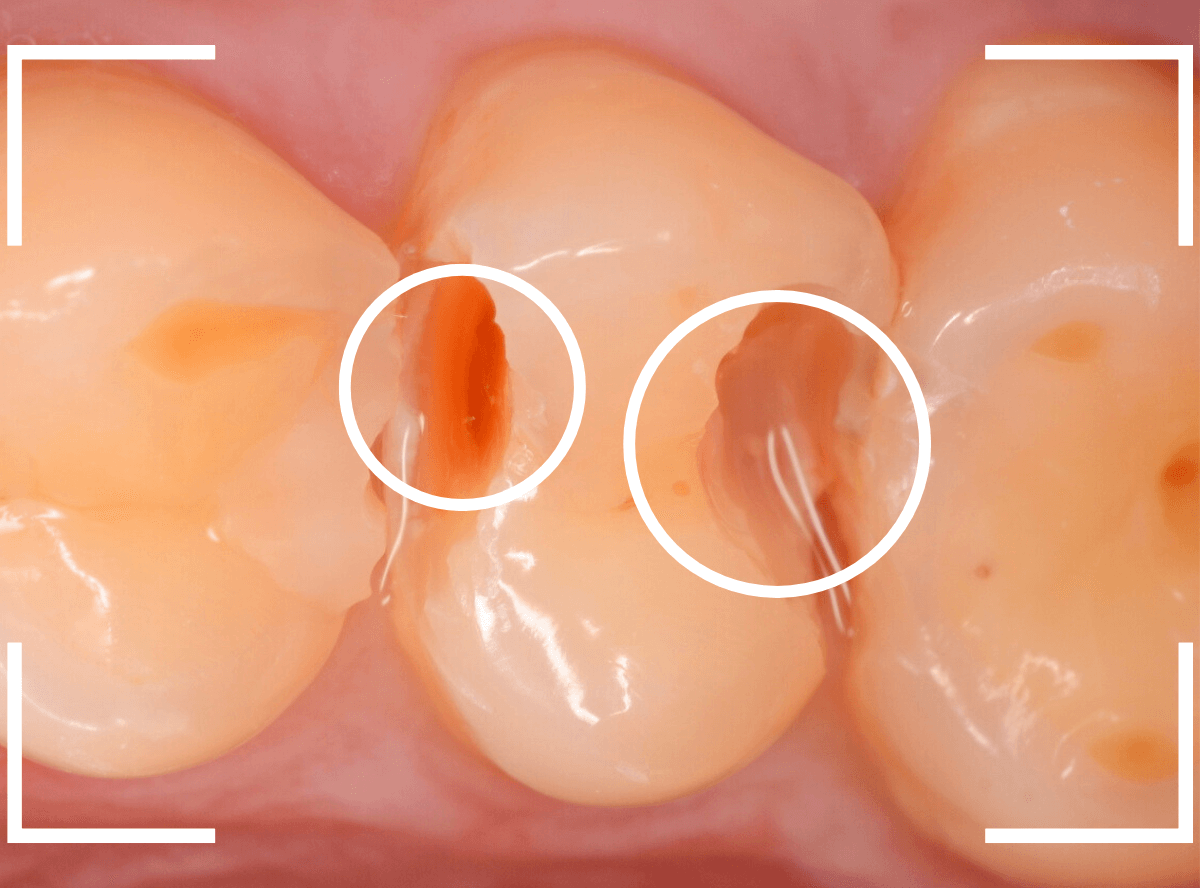

虫歯の治療を開始します。

隣の歯とのすき間を中心に広い虫歯になっていました。